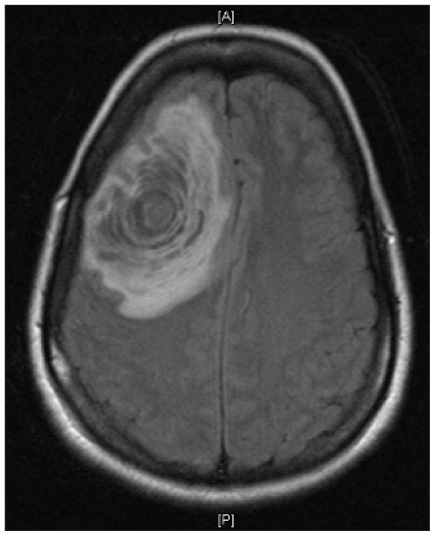

Patient 3 was a previously healthy 35-year-old woman who presented with new-onset generalized tonic-clonic seizures and headaches. Magnetic resonance imaging scans showed a large right frontal mass with surrounding edema and a mild midline shift (Fig. 1). The patient underwent a diagnostic stereotactic brain biopsy. Low-grade glioma and reactive gliosis were among the likely differential diagnoses. Permanent section showed a demyelinating lesion. In retrospect, the appearance of the mass was similar to that seen in Balo concentric sclerosis in which there are large regions of alternating zones of demyelinated and myelinated white matter.

Fig. 1.

A T1-weighted magnetic resonance imaging scan showed a right frontal lesion with midline shift.